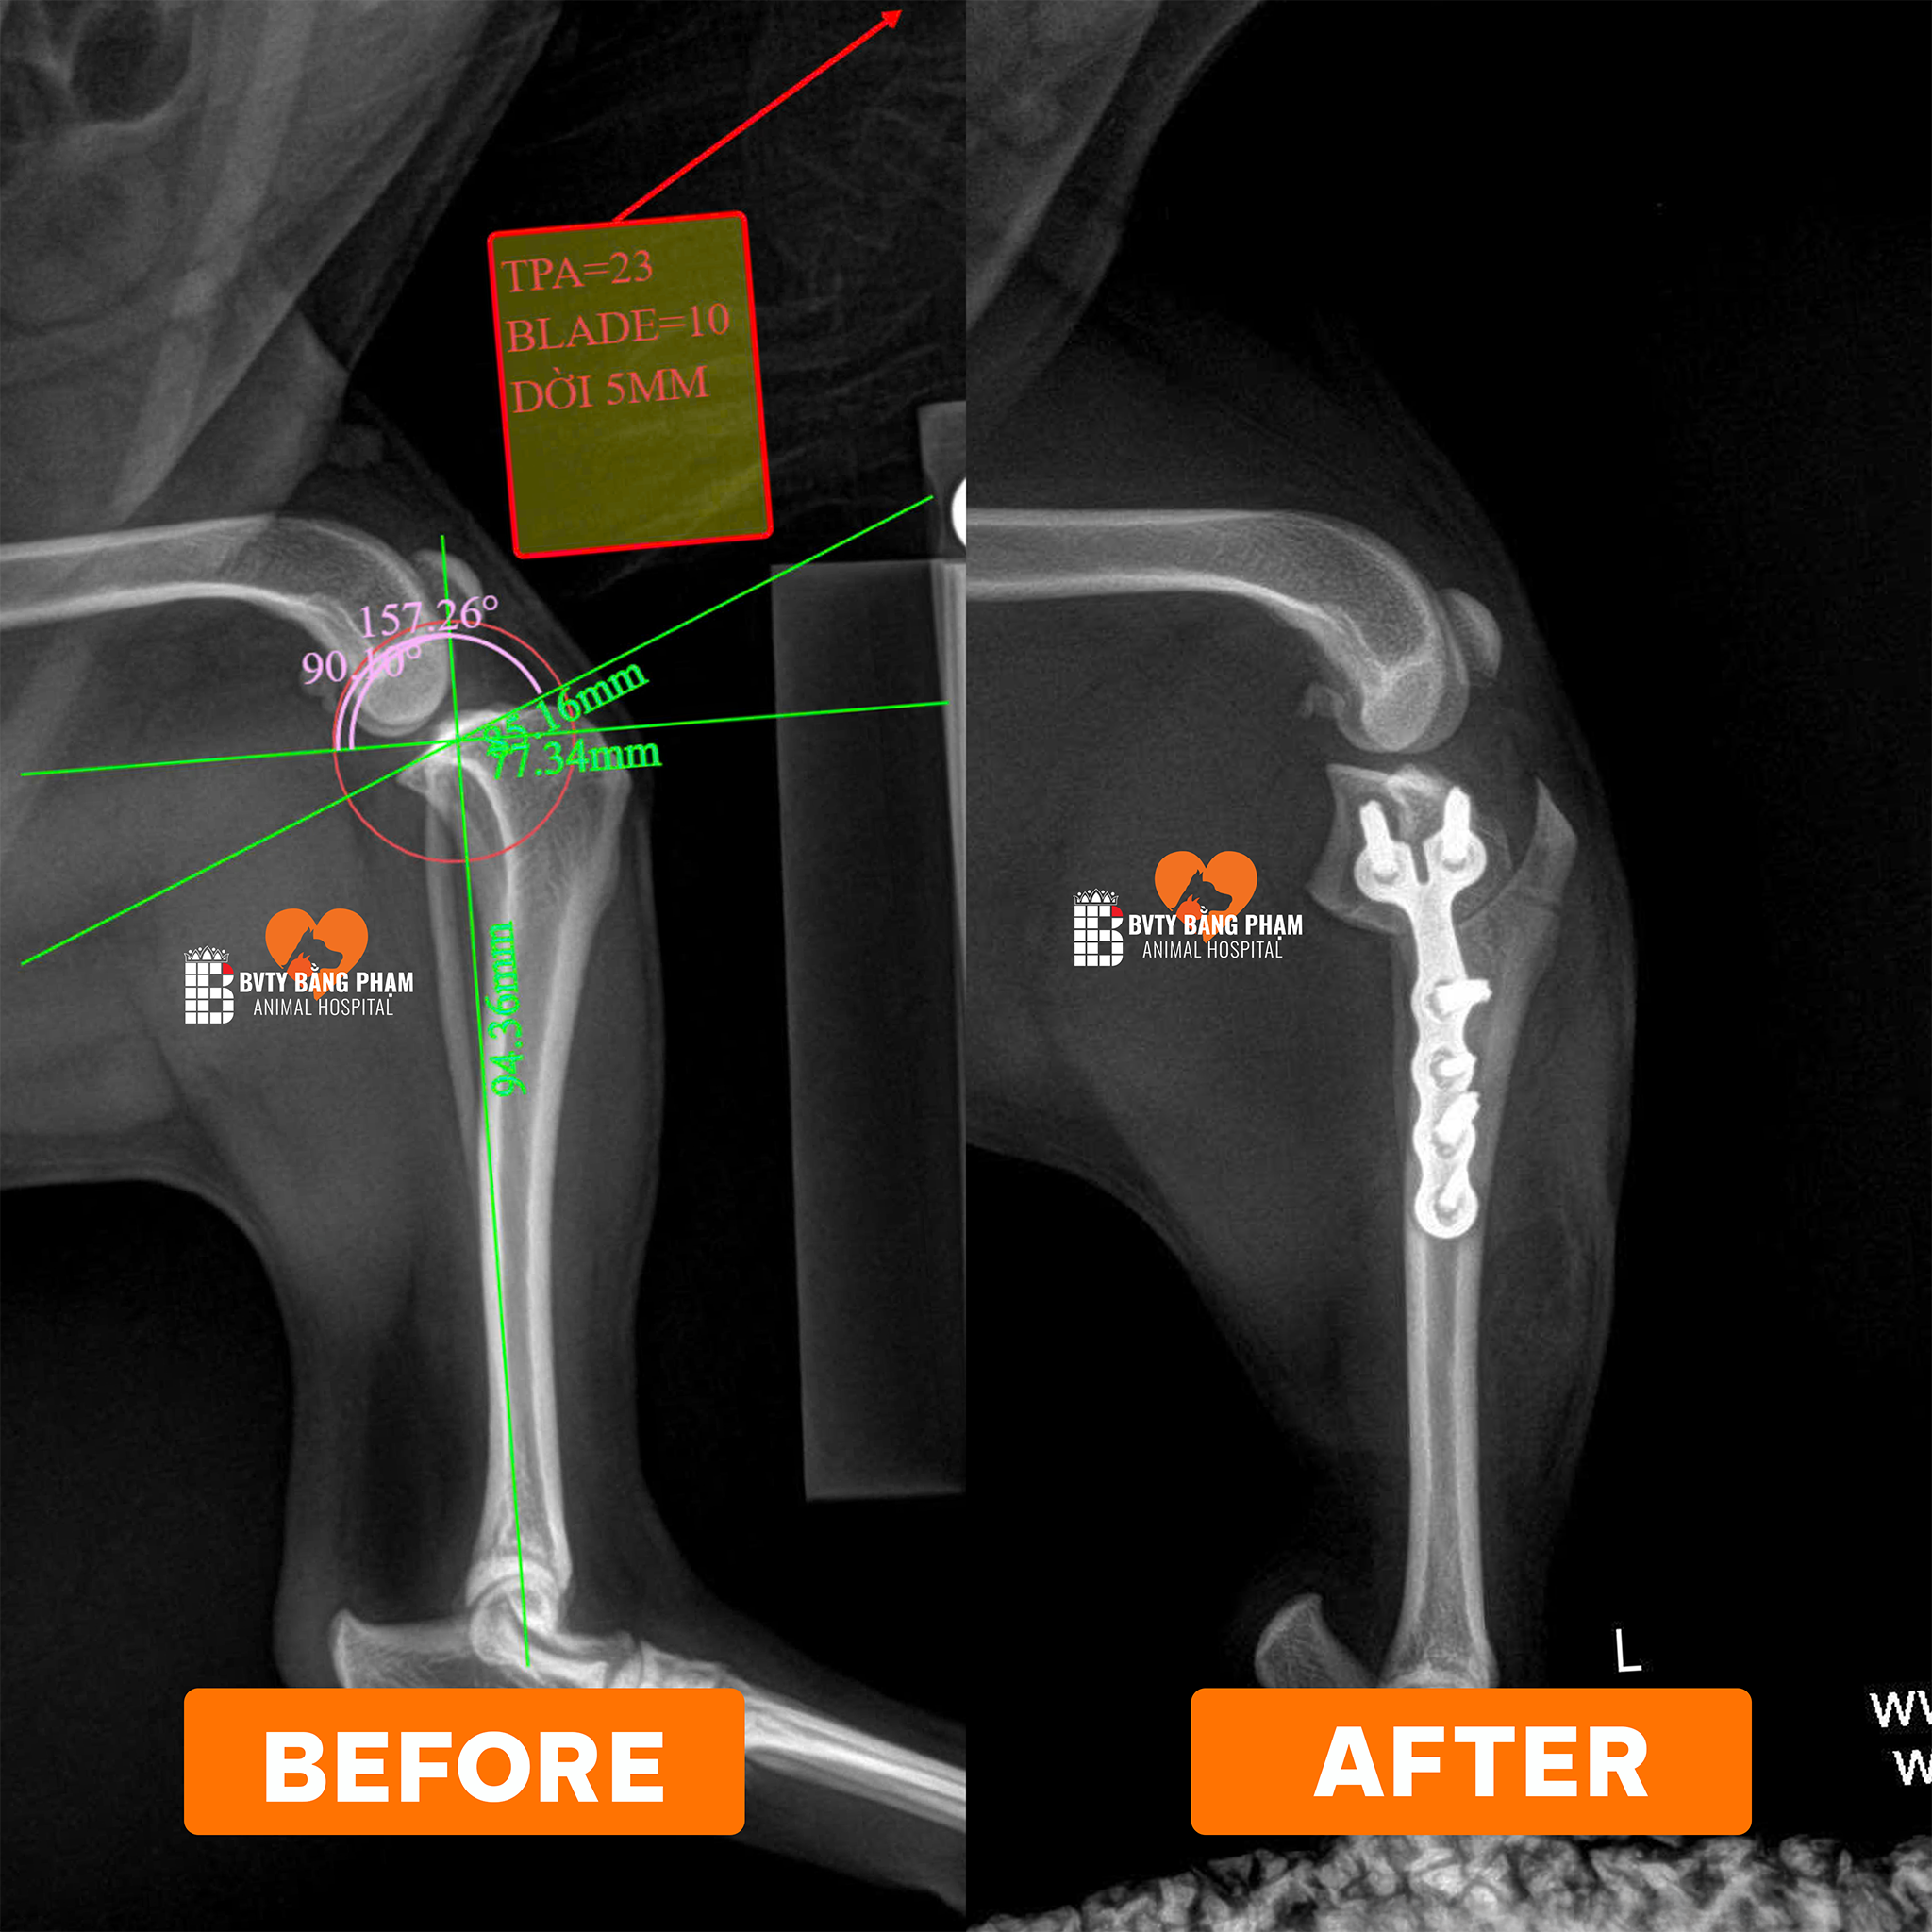

Tại Bệnh viện Thú Y Bằng Phạm, đội ngũ bác sĩ chuyên khoa chỉnh hình đã tiếp nhận và điều trị nhiều ca đứt dây chằng chéo trước (CCL) bằng kỹ thuật TPLO (Tibial Plateau Leveling Osteotomy) — một trong những phương pháp hiện đại và hiệu quả nhất hiện nay. Theo tài liệu chuyên môn, TPLO giúp thay đổi góc của mặt trượt xương chày, từ đó loại bỏ lực trượt (tibia thrust) lên khớp gối và tái lập sự ổn định mà không cần “cố gắng tái tạo hay khâu dây chằng” như cách truyền thống.

Khám – chụp X-quang, đánh giá góc xương chày, mức độ thoái hóa khớp gối

Phẫu thuật TPLO: cắt một đoạn xương chày theo hình bán nguyệt, xoay đoạn này để tạo góc mới phù hợp, sau đó cố định bằng bản kim loại và vít